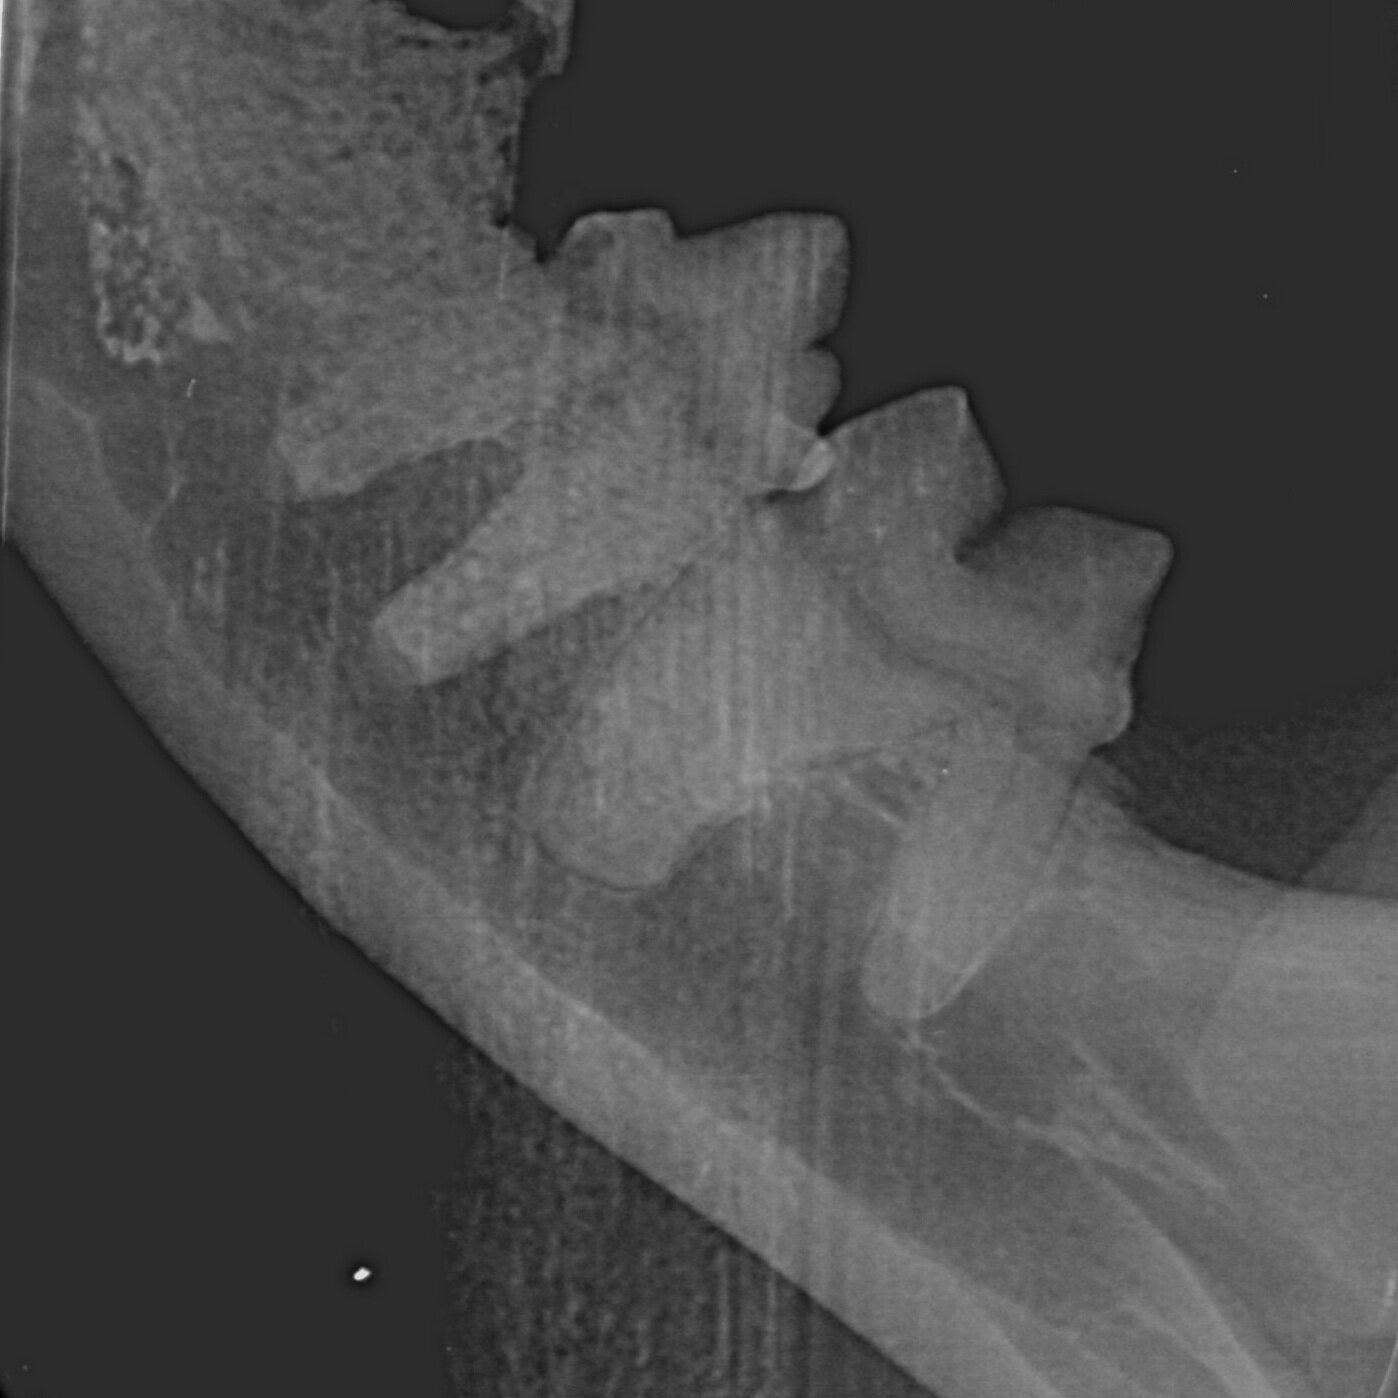

Case Study: Elbow Wound

This is a short case study about Keiser, one of SHAK’s golden oldie residents, who presented with a significant lameness in early November. Here is what we found!